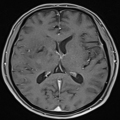

| 影像学检查:(点击查看大图) | 右侧基底节区及海马可见团状异常信号,T1WI呈稍低信号,T2WI呈稍高信号,内见小片状T1低T2高信号影;右侧额叶可见长径约9mm的结节状异常信号,T1WI呈稍低信号,T2WI呈稍高信号。 MRS示右侧基底节区病变较对侧正常区域,NAA(N-乙酰天冬氨酸)峰减低,Cho(胆碱)及Cr(肌酐)峰增高。 DTI示右侧基底节区皮质纤维束部分纤维中断; ASL示右侧基底节区CBF增高,右侧海马区CBF明显增高,右侧额叶结节CBF略增高。考虑肿瘤性病变,胶质瘤可能性大。 |